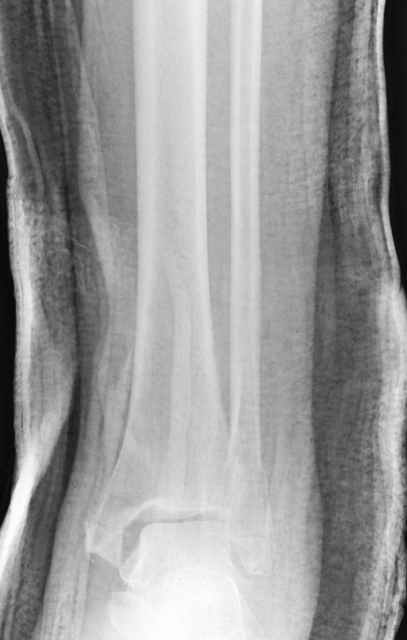

Я вот все в толк не возьму смысл отдельной фиксации малоберцовой кости пластинкой, если все равно будет аппарат с фиксацией стопы, т.е. возможностью провести спицы в пятку, таран, наружную лодыжку и еще черт-те куда. Остеосинтез пластинкой выглядит логичным в случае, когда наружная фиксация планируется как временная. Но тут-то аппарат будет окончательным фиксатором.

Еще, кстати, о фиксации лодыжки, если уж непременно хочется ее отдельно стабилизировать - при таком характере перелома замечательно должен сработать предложенный проф. Лазаревым с соратниками способ фиксации напряженной V-образной спицей. Опять же, открытая репозиция не нужна, мы делаем непрямую репозицию именно аппаратом. В приложении пример, там перелом малоберцовой куда менее поперечный, чем в данном случае, но все равно получилось закрыто без пластинки.

I can't realize why plate fibula separately if anyway external fixator including the foot is planned, i.e. one may insert wires to the talus, calcaneus, lateral malleolus and anywhere else. Plating looks reasonable if only temporary ex-fix is planned, but in the case it will be definitive.

A propos fibular fixation if one is eager to stabilize it separately. In the fracture pattern a way of closed fixation by V-shaped stressed wire (advanced by colleagues from Moscow, prof. Lazarev A.F. et al.) must be excellent. We use indirect closed reduction by the external fixator. Example attached, that fibular fracture is even more suitable for plating but the wire did the job.

Дистракция в аппарате или на вытяжение результат - лигаментотаксис, посмотреть бы, как сегодня расположены отломки.